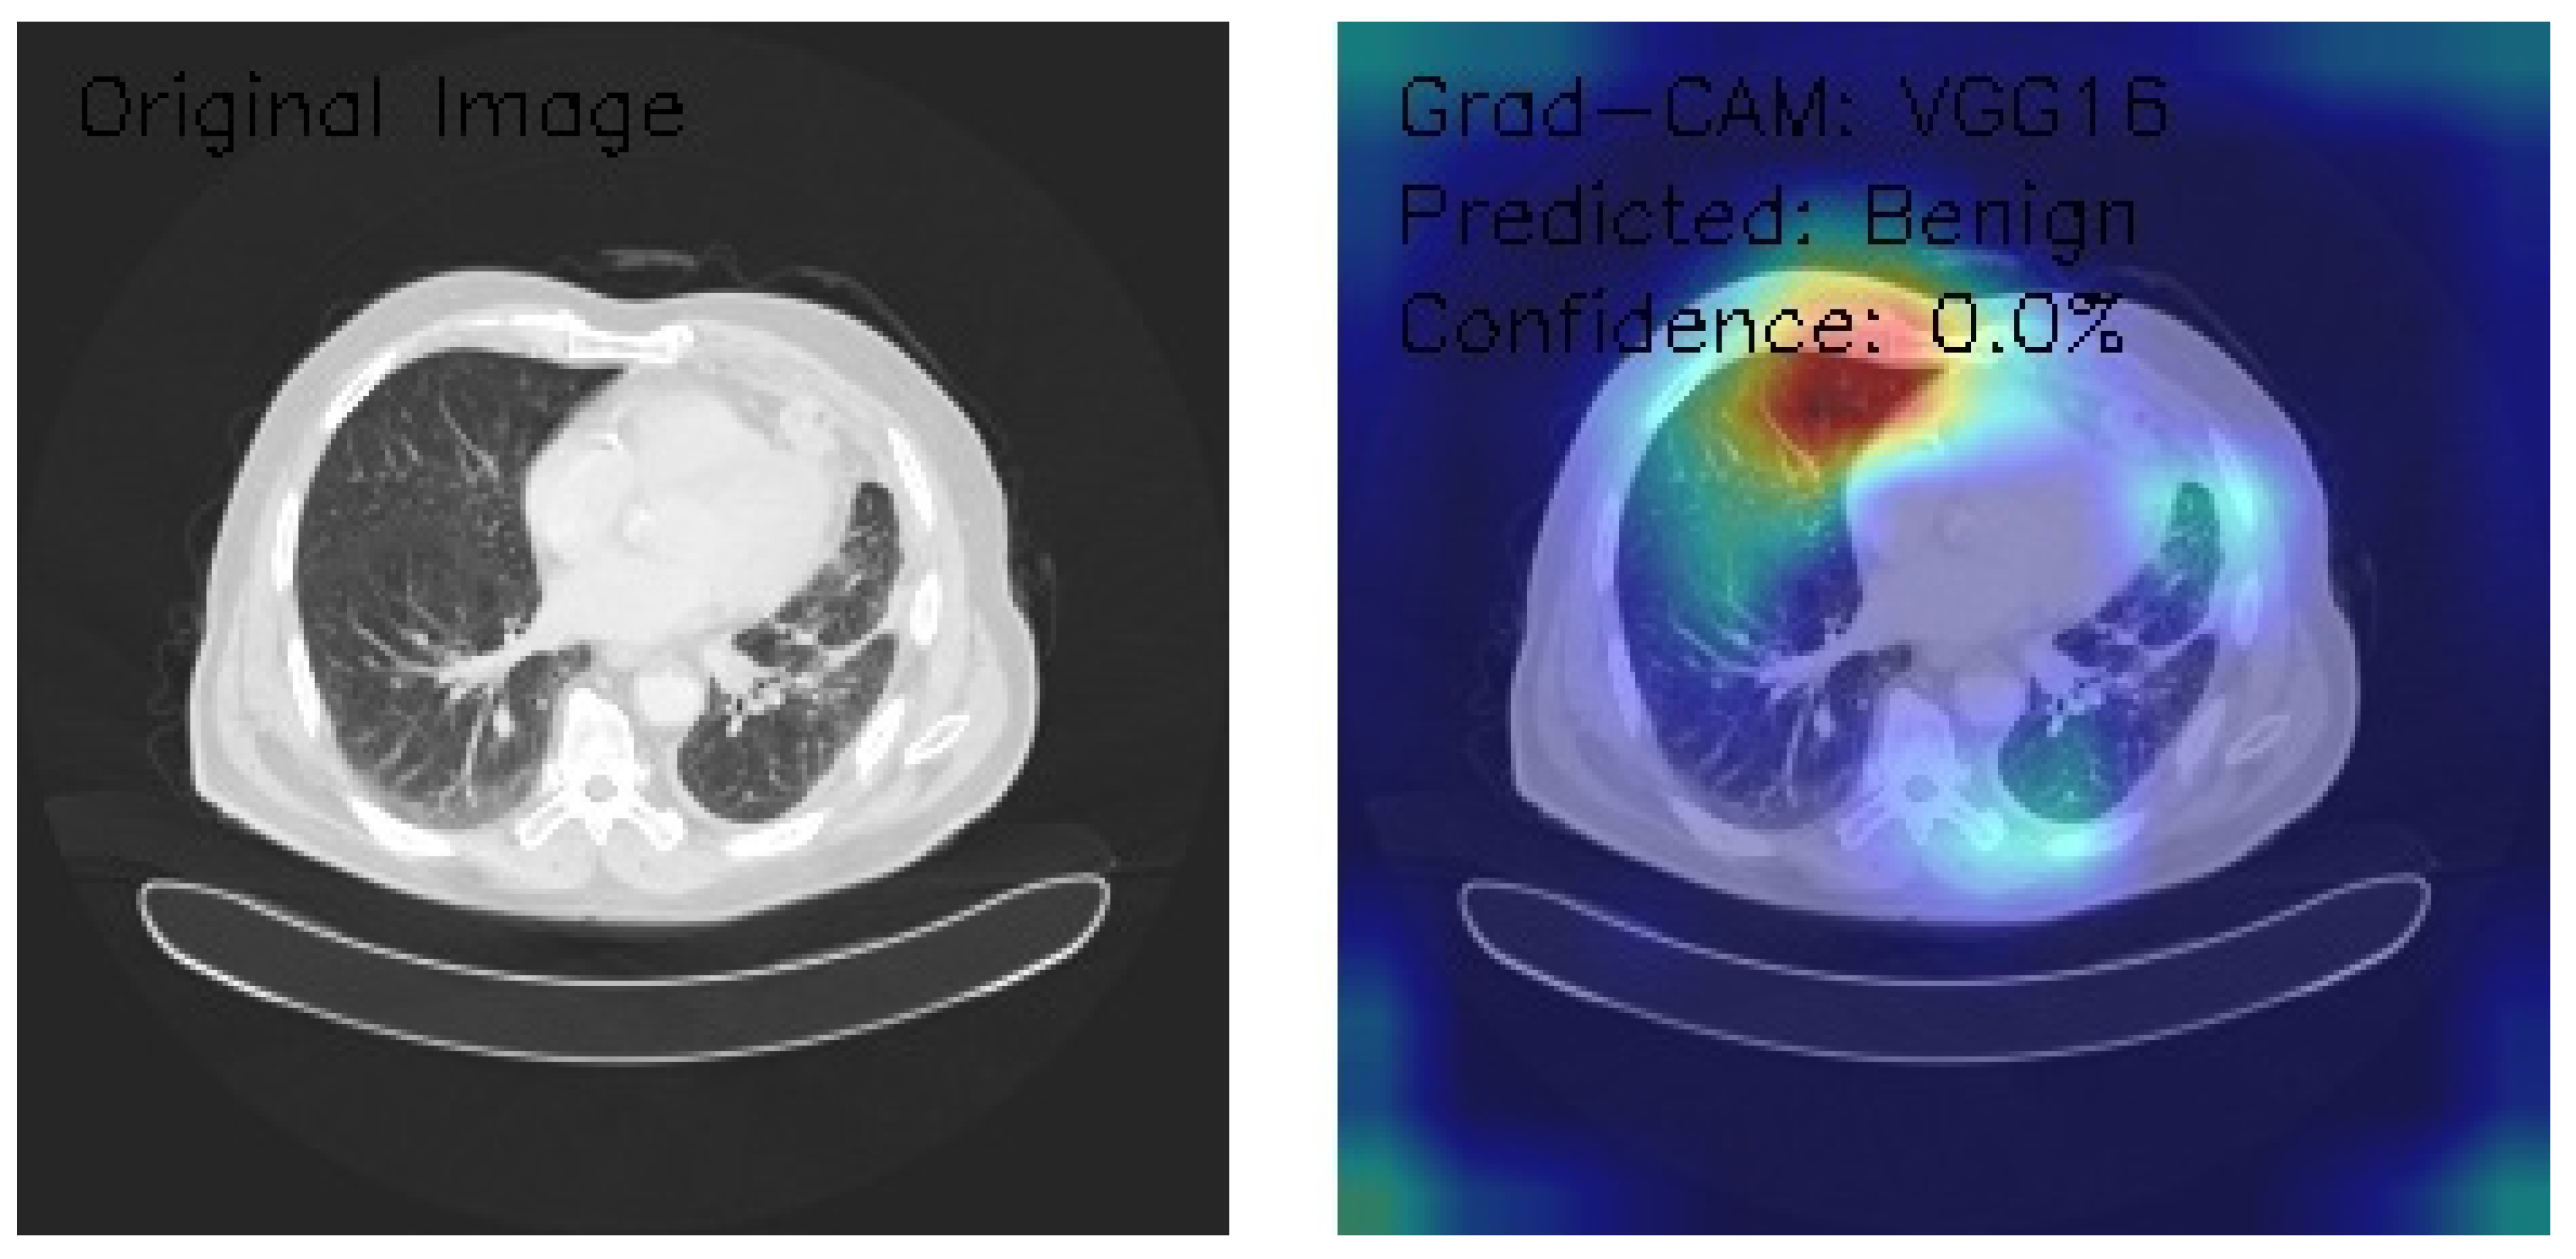

VGG16 Model Analysis of Lung CT Images with Grad-CAM Visualization

The results section of this analysis provides a detailed examination of three axial chest CT images analyzed through the VGG16 architecture, a widely recognized convolutional neural network model. We employed Grad-CAM, an advanced visualization technique, to gain insights into the model’s decision-making processes and focus areas. This method highlights the regions of the input images the model considers most significant when making predictions, offering a comprehensive view of its attention patterns. By integrating Grad-CAM with the VGG16 framework, this analysis illustrates the model’s effectiveness in interpreting medical imaging data and provides a transparent mechanism to evaluate its decision rationale. The findings presented aim to shed light on the nuanced interactions between the neural network and the image features, contributing to the broader understanding of AI-assisted diagnostic methodologies.

Figure 15 shows the analyzed CT image presenting scattered nodular opacities, with Grad-CAM visualizations emphasizing bilateral upper lung fields and an intense, asymmetric activation pattern, predominantly on the right side. The model classifies the image as Normal with a confidence score of 0.0% despite notable focal areas of high activation marked by yellow-red coloration. This discrepancy between the detected features and classification outcome highlights potential limitations in the model’s ability to translate activation insights into reliable predictions. The findings underscore the need for recalibration and refinement of classification and confidence scoring mechanisms to improve diagnostic accuracy and clinical reliability.

Figure 15.

Grad-CAM visualization (VGG16) highlighting nodular opacities in bilateral upper lungs with asymmetric right-side activation. (Source: author’s analysis from data, 2024).

The VGG16 model, applied to three chest CT images with Grad-CAM visualizations, demonstrates strong capabilities in localizing anatomical features but struggles with reliable classification due to uniformly low confidence scores. Image A, showing scattered nodular opacities, reveals intense bilateral upper lung activation with a predominant right-sided focus, yet is classified as Normal with 0.0% confidence. Image B highlights peripheral lung field activation and lateral chest wall emphasis in the presence of interstitial patterns, classified as Benign with 0.0% confidence. Image C, featuring clear lung fields, displays focal activation in the right upper lung and hilar regions, but is similarly classified as Benign with 0.0% confidence. While the model excels in highlighting regions of interest with precise and consistent attention patterns, its limited confidence and conservative classification behavior highlight the need for calibration and optimization. These findings suggest potential utility in feature detection and initial screenings, provided enhancements to confidence scoring and classification thresholds are implemented.